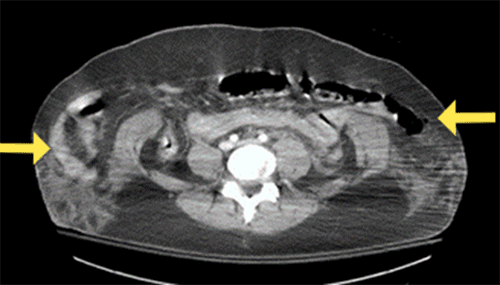

Figure 1. Abdominal/Pelvic CT Scan. Published with Permission

This image demonstrates herniation of viscera through the abdominal musculature with markedly lateral displacement into the subcutaneous space, as indicated by the yellow arrows

A 31-year-old female presented to the emergency department as a trauma activation after a motor vehicle crash. Immediately after the accident, the patient endorsed severe abdominal pain radiating across the lower abdomen. On primary survey, she was found to have ecchymosis over her right breast, sternum, and lower abdomen in the distribution of where her seat belt was in place. These findings were consistent with a “seat belt sign,” a pattern of injury associated with high-impact trauma after a motor vehicle collision; it’s presence demonstrated a high likelihood of underlying visceral injury. Given these findings and her hemodynamic stability, she was expedited to the CT scanner as early diagnosis of her injuries was crucial in her treatment course. CT imaging revealed complete disruption of the abdominal wall musculature with transverse dehiscence at the approximate level of the umbilicus, retraction of both rectus abdominis muscles, and violation of the peritoneum. Fluid and gas were found within the peritoneal space, which was hypothesized to be from hollow viscus injury.